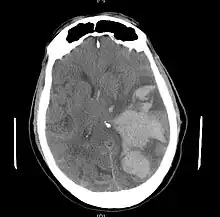

Brain herniation is a potentially deadly side effect of very high pressure within the skull that occurs when a part of the brain is squeezed across structures within the skull. The brain can shift across such structures as the falx cerebri, the tentorium cerebelli, and even through the foramen magnum (the hole in the base of the skull through which the spinal cord connects with the brain). Herniation can be caused by a number of factors that cause a mass effect and increase intracranial pressure (ICP): these include traumatic brain injury, intracranial hemorrhage, or brain tumor.[1]

Treatment

Treatment involves removal of the etiologic mass and decompressive craniectomy. Brain herniation can cause severe disability or death. In fact, when herniation is visible on a CT scan, the prognosis for a meaningful recovery of neurological function is poor.[2] The patient may become paralyzed on the same side as the lesion causing the pressure, or damage to parts of the brain caused by herniation may cause paralysis on the side opposite the lesion.[11] Damage to the midbrain, which contains the reticular activating network which regulates consciousness, will result in coma.[11] Damage to the cardio-respiratory centers in the medulla oblongata will cause respiratory arrest and (secondarily) cardiac arrest.[11] Investigation is underway regarding the use of neuroprotective agents during the prolonged post-traumatic period of brain hypersensitivity associated with the syndrome.[17]